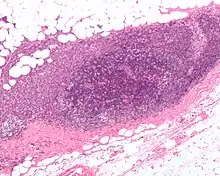

A micrograph showing an adenocarcinoma of the breast (dark pink) in a lymph node (purple) and extending into the surrounding fat (white, chicken-wire appearance). H&E stain.